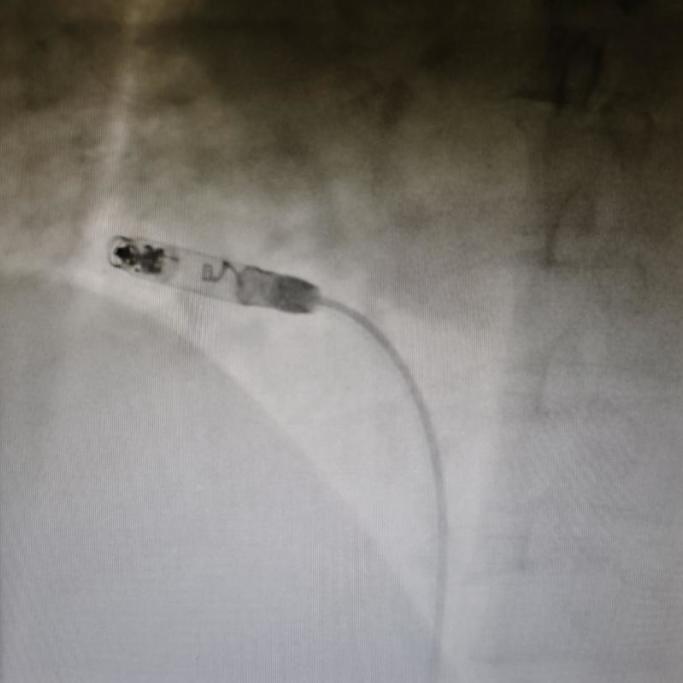

猪尾左前斜造影

左前斜:递送鞘造影定位植入位点